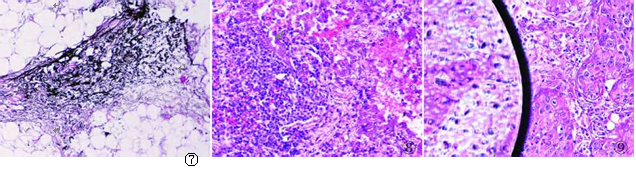

图7动脉血管周围组织切HE染色,甲醛色素沉积,影响切片清晰和美观

图8肺组织切片HE染色,染片后脱水不彻底,出现镜下水印

图9肾脏组织切片HE染色,出现气泡,既影响美观,又妨碍阅片